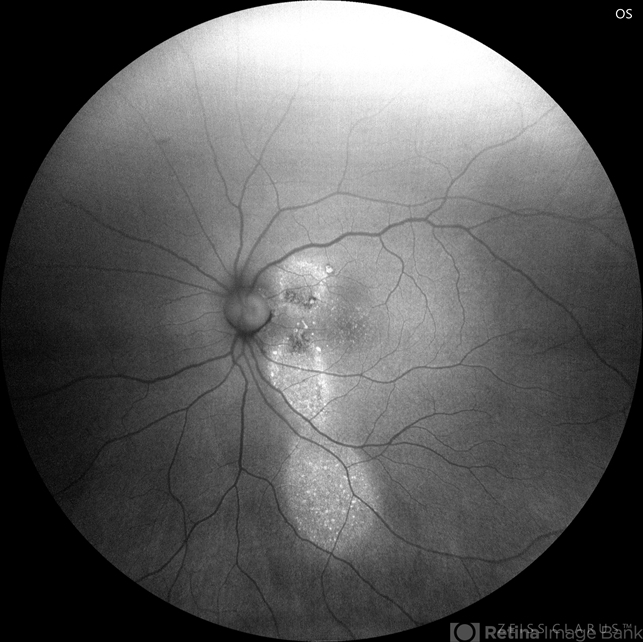

- Central Serous Chorioretinopathy (CSR), idiopathic central serous choroidopathy (ICSC), fundus autofluorescence (FAF), autofluorescence imaging

Zeiss clarus 700 - Description

- 37-year male with chronic CSR